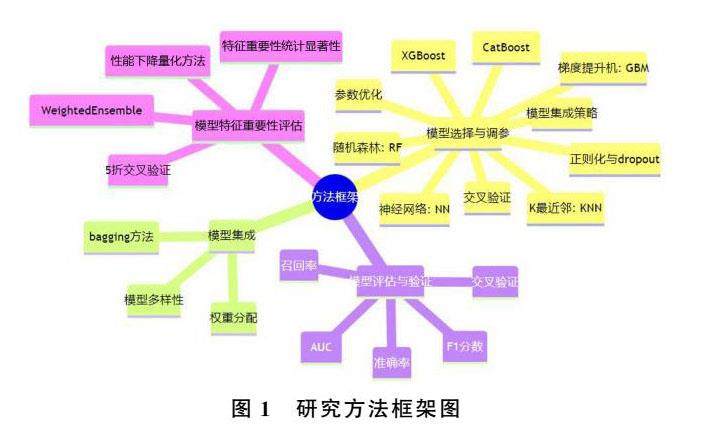

论著 | 基于深度学习和机器学习的胃癌预测模型构建及评估

论著 | 基于深度学习和机器学习的胃癌预测模型构建及评估